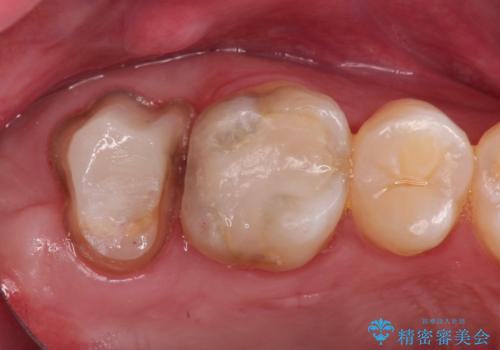

歯肉に埋もれたマージンライン 奥歯の被せもの

- 被せものが取れたことを主訴に来院されました。

以前の被せもののマージンは歯肉縁下に深く形成され、根尖病変も認めたため、根管治療(林先生に依頼)、歯周外科、PGAクラウンにて修復治療を行いました。